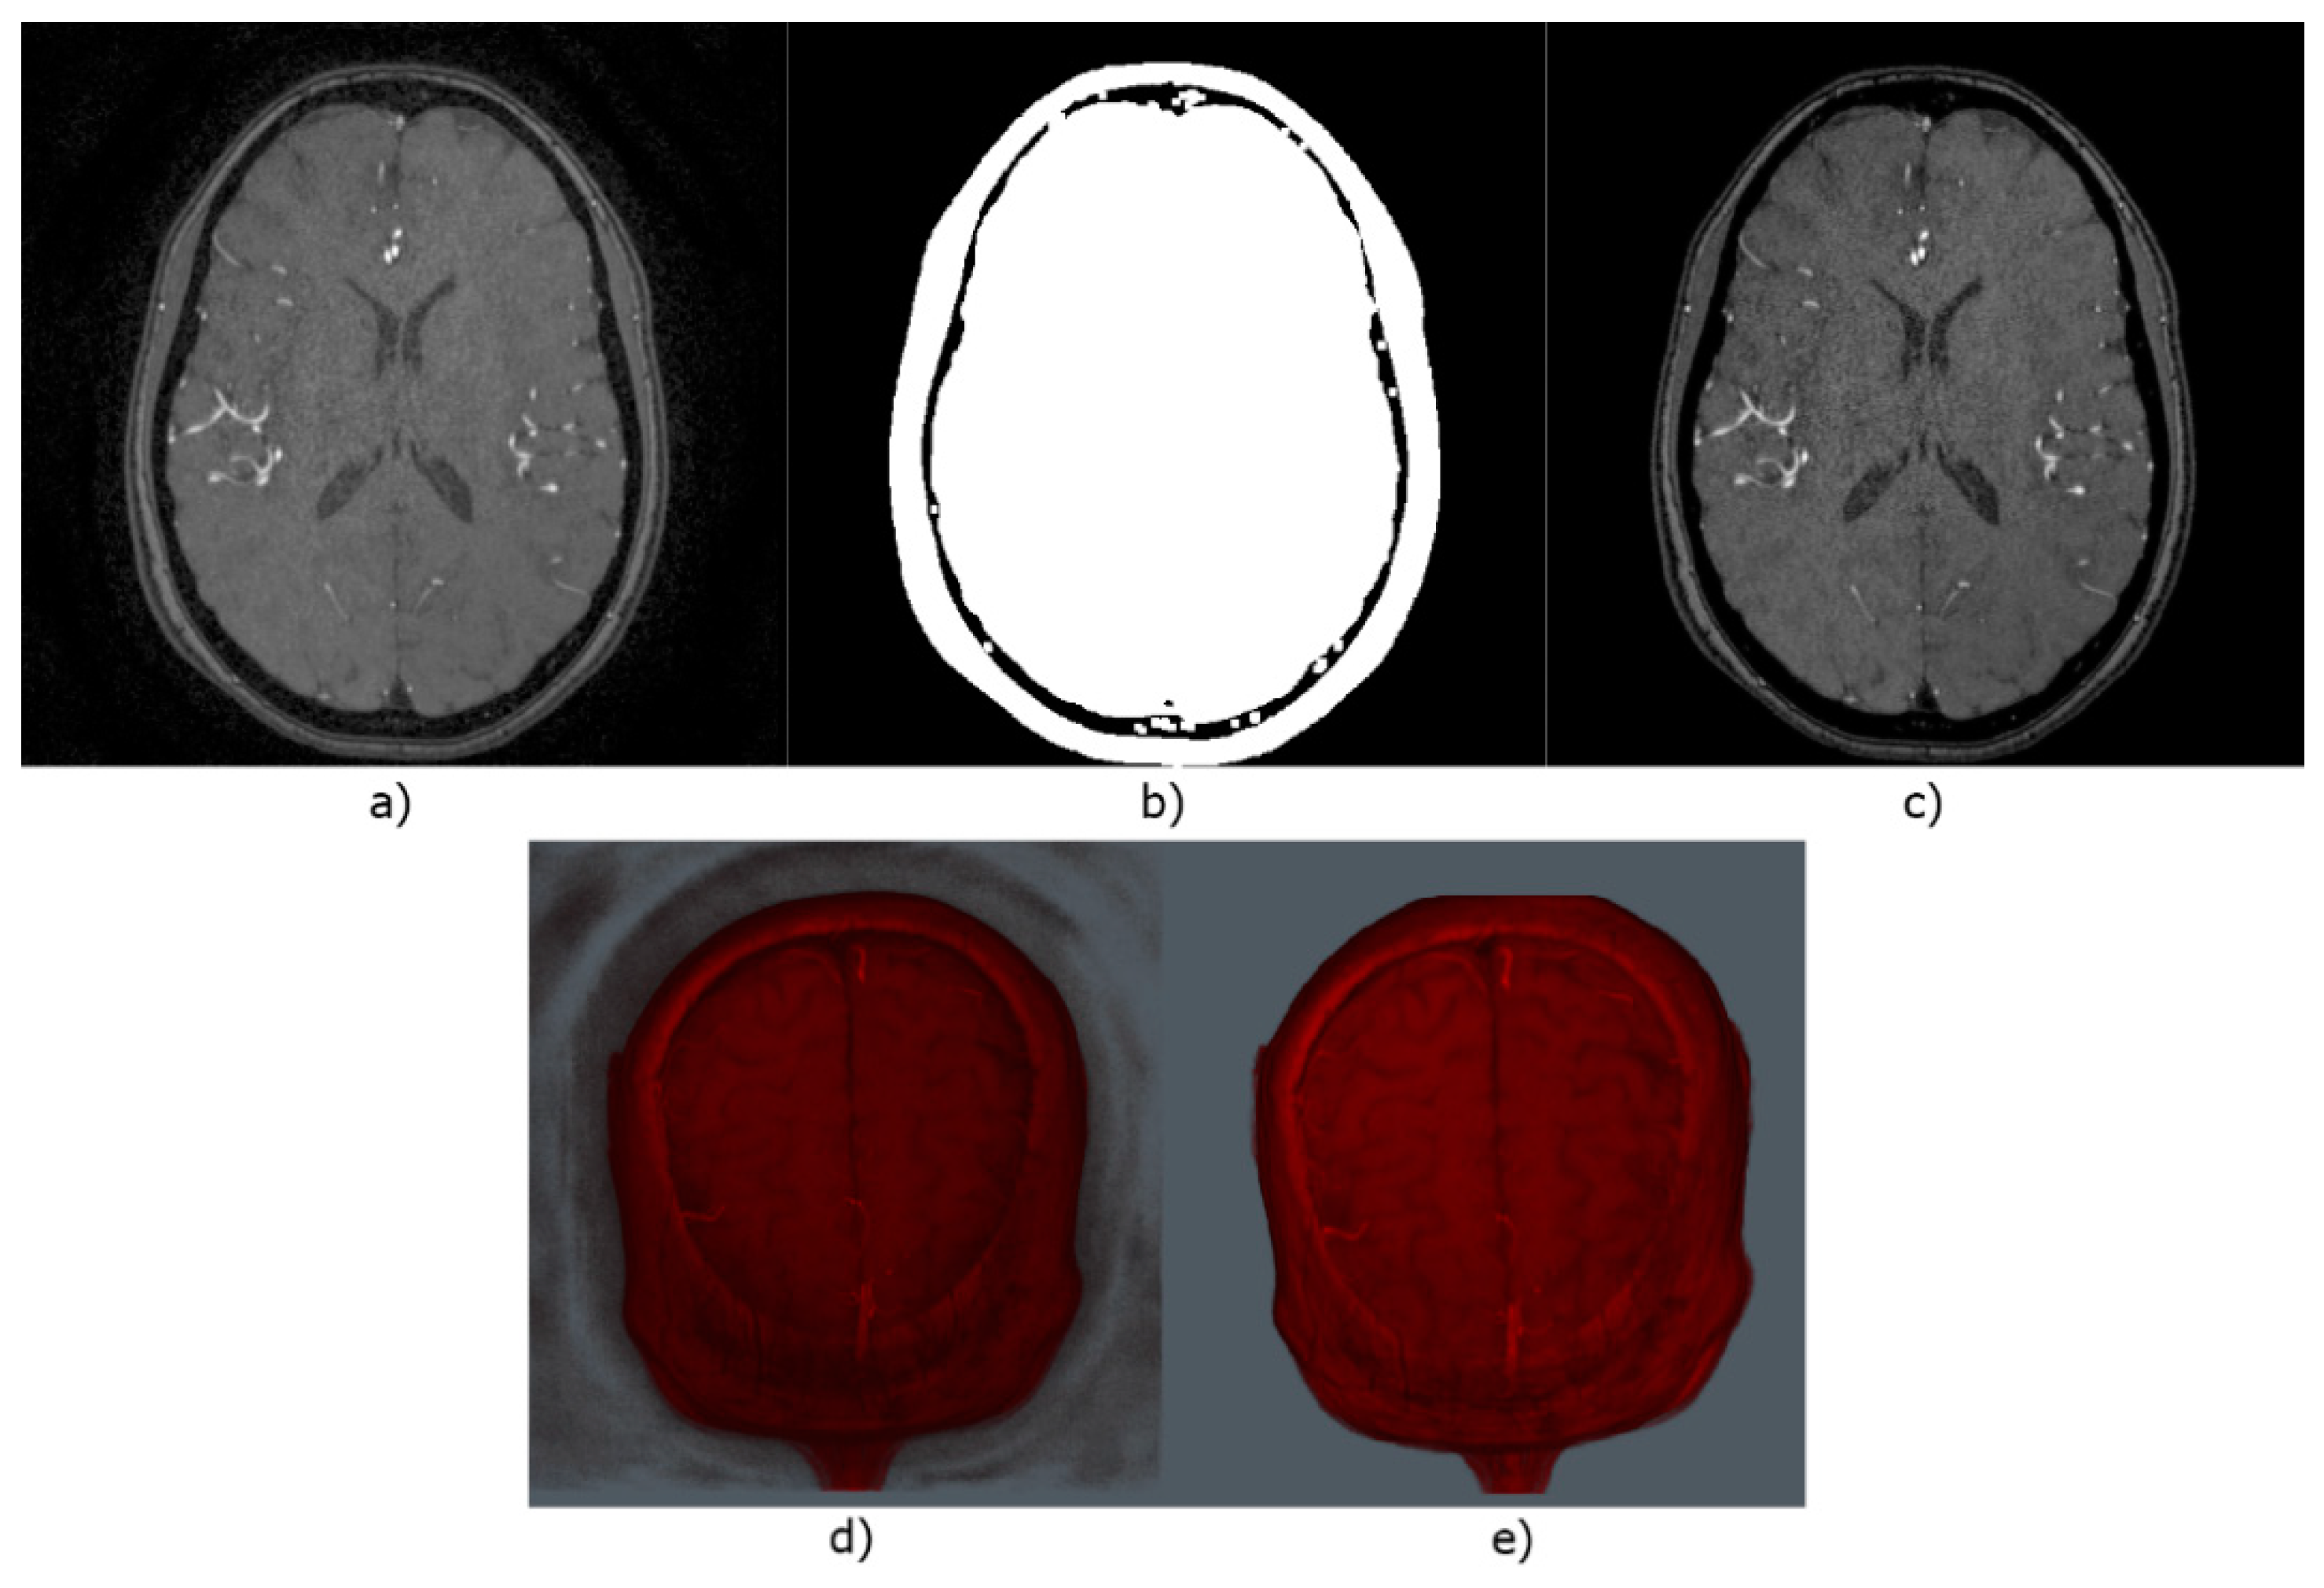

- Image preprocessing

- MRA Images